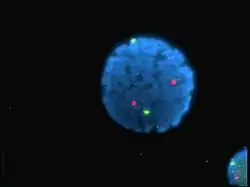

Galeria de imagens

Núcleo de linfócitos humanos coloridos com DAPI com o cromossoma 13 (verde) e 21 (vermelho) sondas centrómero hibridizadas (hibridização fluorescente in situ (FISH)) -